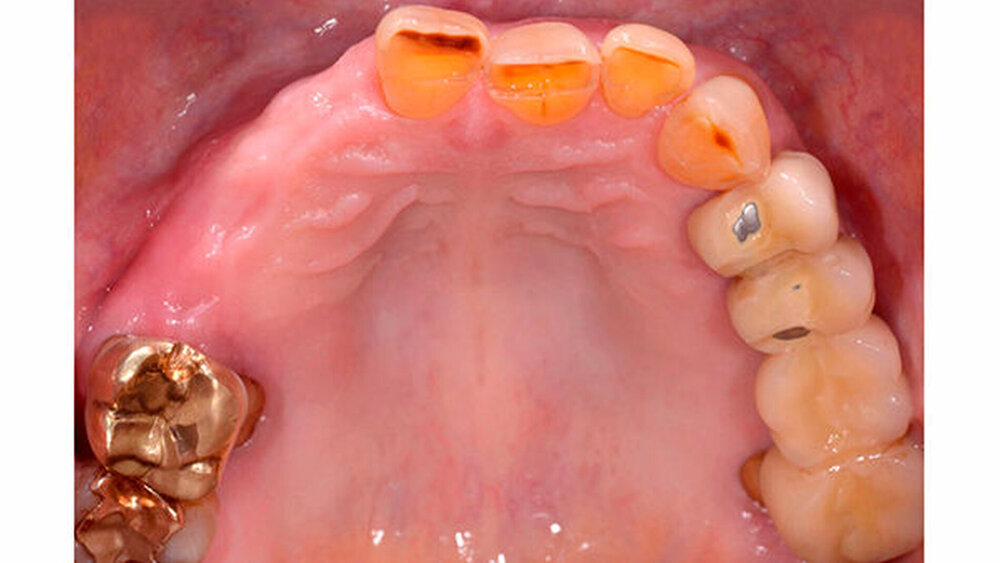

Dr. Sebastian Schwindling (Universität Heidelberg) ist Young-Esthetics-Preisträger 2017. Sein Fall ist komplex: die Gesamtrehabilitation eines parafunktionell vorgeschädigten Gebisses. "Selbst erfahrene Zahnärzte würden sich damit nicht leicht tun", heißt es aus der Jury. Hier stellt der Preisträger seine Arbeit vor.